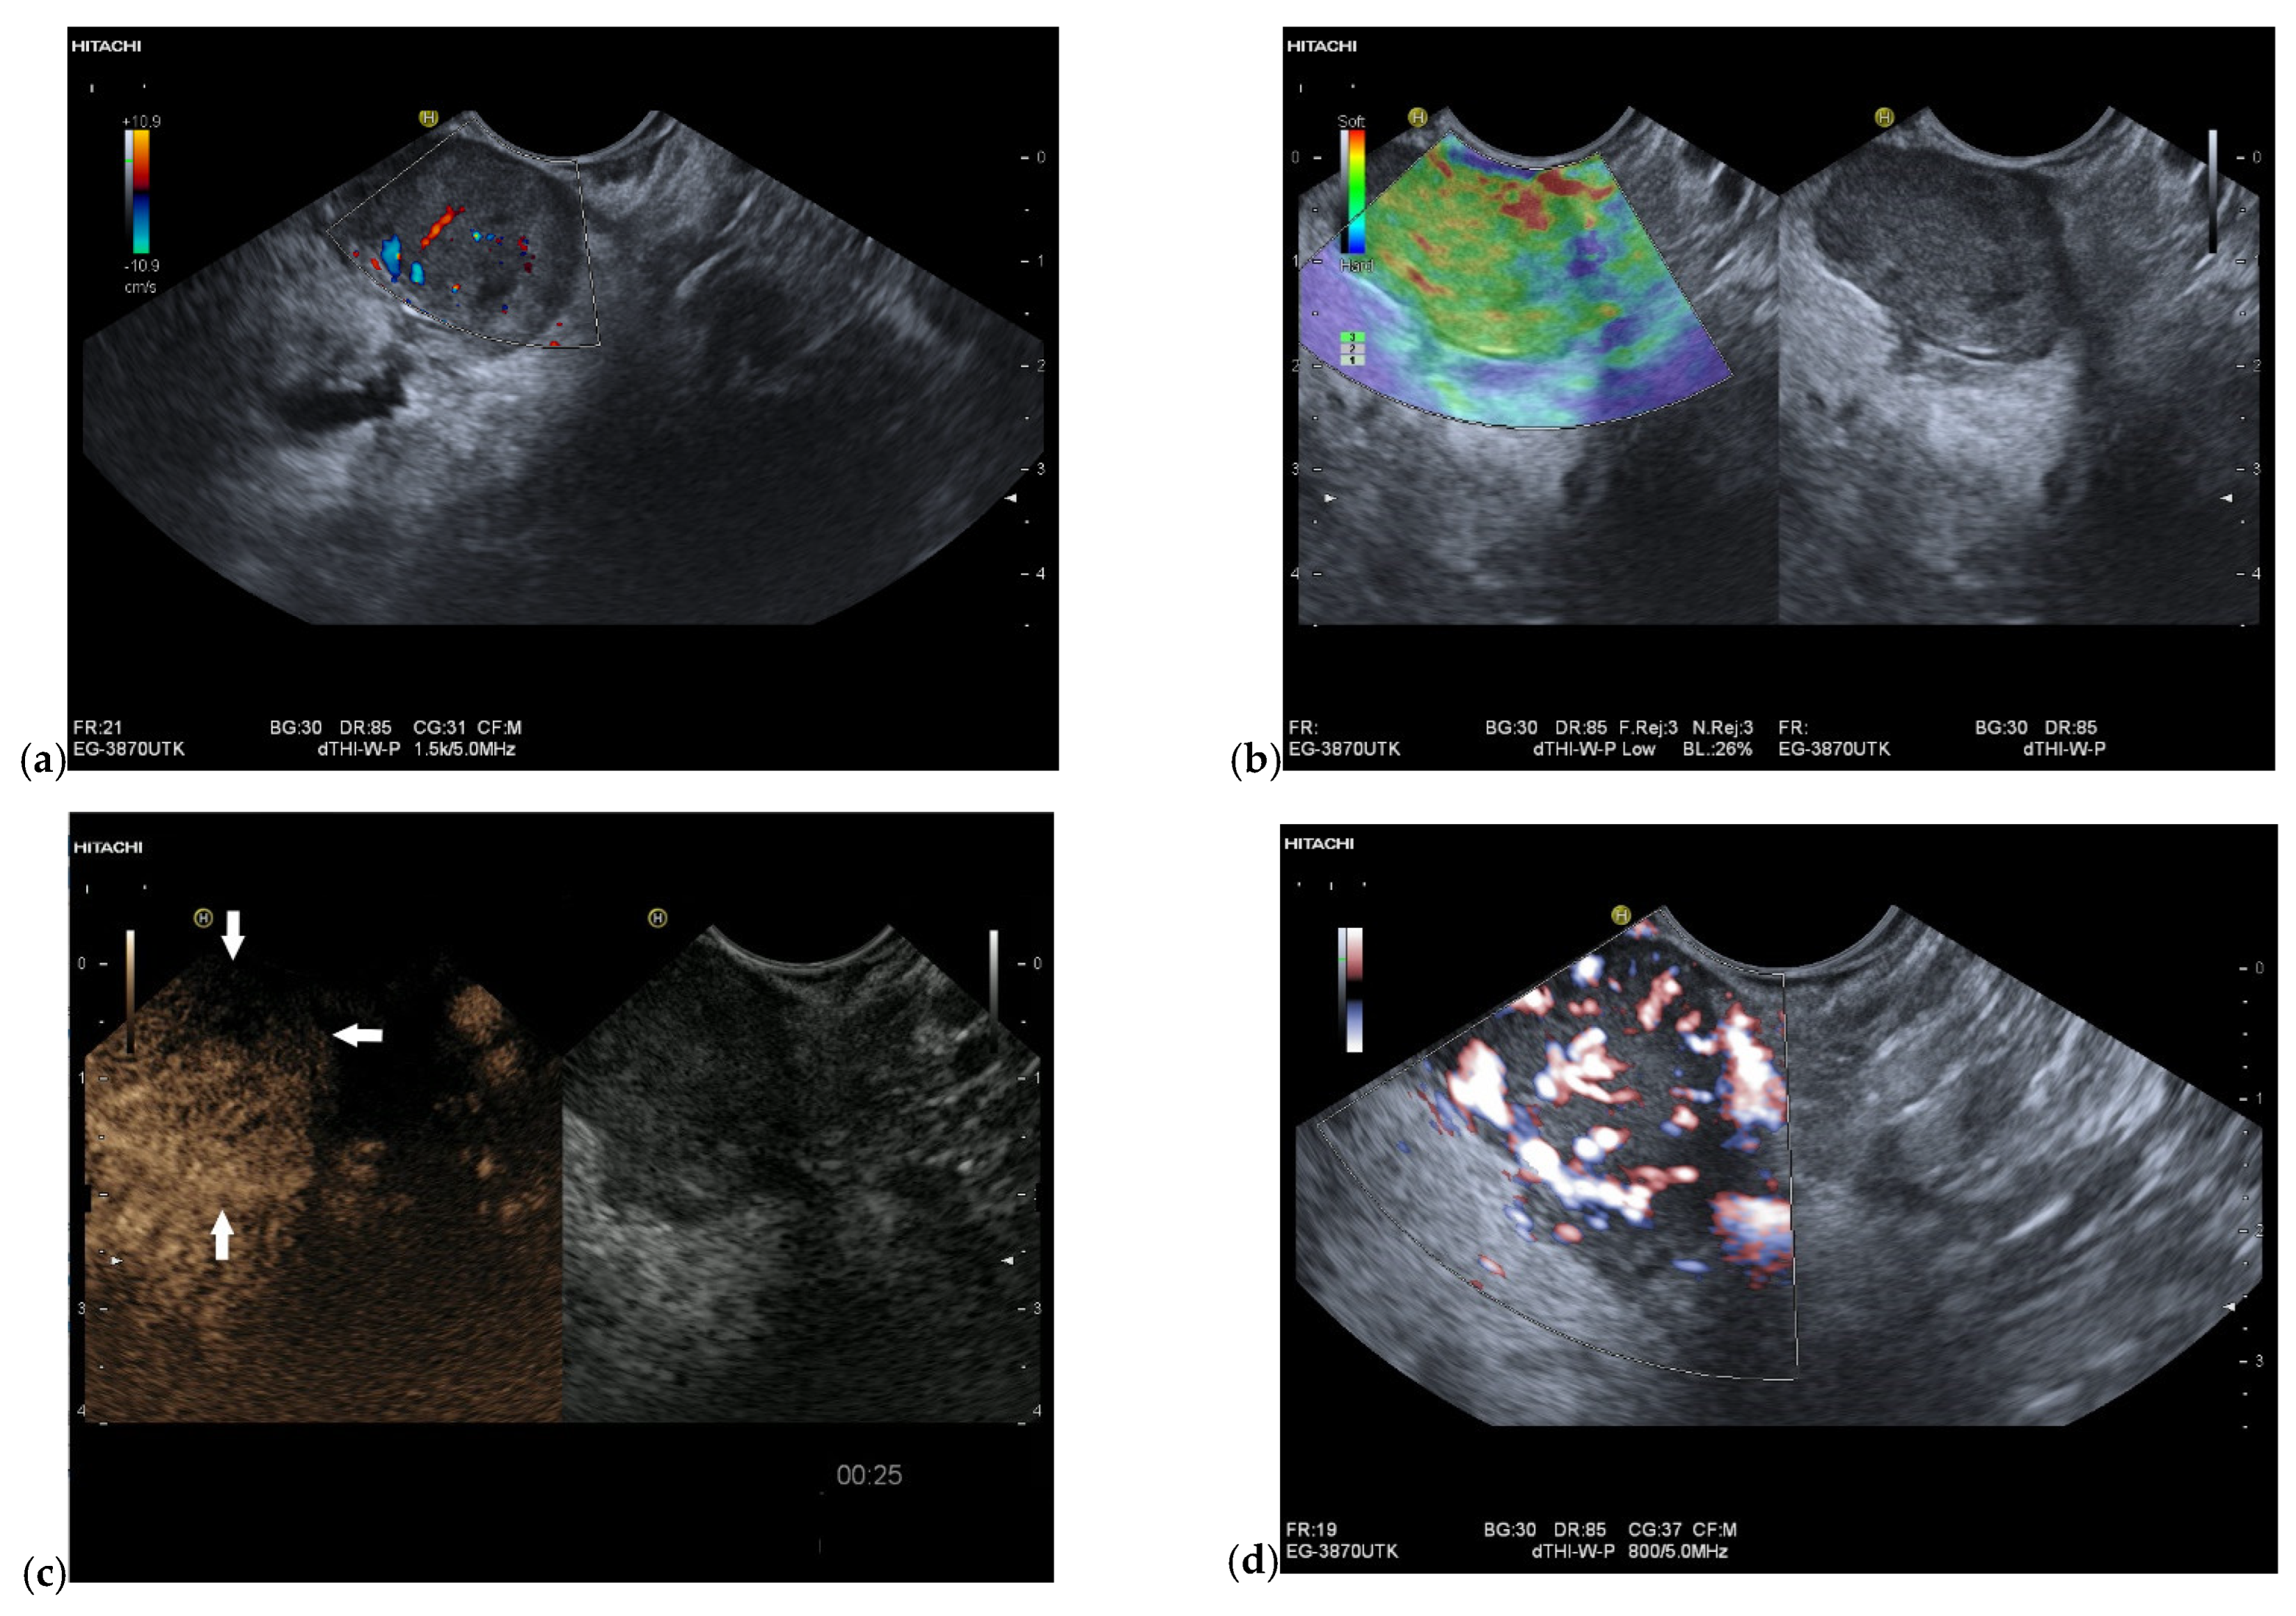

3.4. CEUS and CH-EUS

| Colour Doppler Imaging | RCC metastases are hypervascularized Most other pancreatic metastases are hypovascularized | No hypervascularization | Hypervascularized |

| Elastography (small lesions up to 15 mm) [67] | 41% softer or isoelastic, 59% stiffer compared to pancreatic parenchyma | 4% soft or isoelastic, 96% stiffer compared to pancreatic parenchyma | 64% soft or isoelastic, 36% stiffer compared to pancreatic parenchyma |

| Cases | CEUS | CH-EUS | ||

|---|---|---|---|---|

| Arterial Phase | Venous Phase | Arterial Phase | Venous Phase | |

| RCC metastases [83] (n = 4) | Hyperenhancement, Early | Hyperenhancement | ||

| RCC metastases [61] (n = 3) | Hyperenhancement, homogeneous pattern | Slow washout | ||

| RCC metastasis [86] (n = 1) | Hyperenhancement, Inhomogeneous pattern | No washout | ||

| Melanoma metastasis [63] (n = 1) | Iso- to slightly hypoenhanced | Hypoenhanced | ||

| Melanoma metastasis [87] (n = 1) | Isoenhanced | Hypoenhancement of the peripheral rim, central non-enhancement | ||

| Melanoma metastasis [61] (n = 1) | Isoenhanced, heterogeneous | Fast washout | ||

| SCLC metastasis [83] (n = 1) | Hyperenhancement | Rapid washout | ||

| Breast, ovarian, colon metastases, sarcoma metastases [61] (n = 6) | Hypoenhancement, homogeneous or heterogeneous | Fast or slow washout | ||

| Lymphoma metastasis [61] (n = 1) | Hyperenhancement, homogeneous pattern | Fast washout |